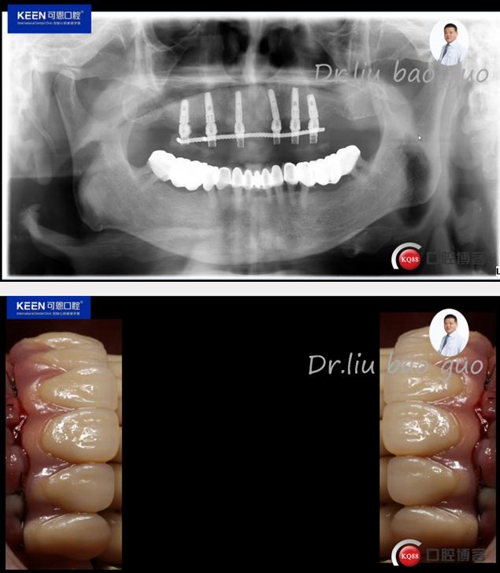

檢 查:顏面對稱,無腫脹、畸形、腫物及竇道;顳下頜關節左右對稱,頦點居中,面下1/3協調。開口度正常無偏斜,雙側關節動度一致,關節無彈響無雜音;咀嚼肌無壓痛;17-27缺失,牙齦無明顯異常,CT示:牙槽骨寬度,高度尚可。

治療方案:建議上頜種植16,14,12,22,24,26,種植后即刻負重

術前照片:

1.jpg

2.jpg

術后照片

12.jpg

13.jpg

14.jpg